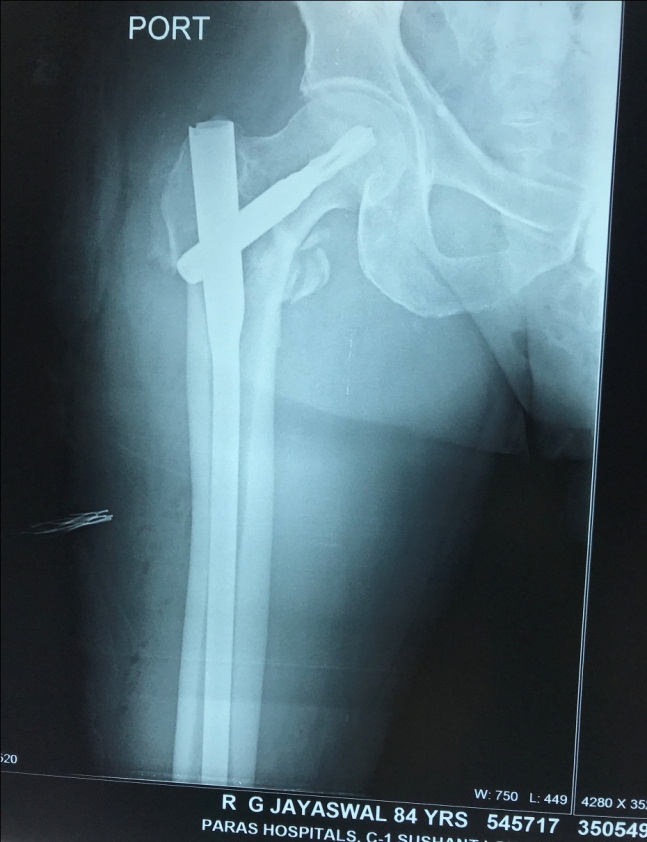

Preop Xray of an osteoporotic hip fracture

osteoporosis

Fixed with a nail